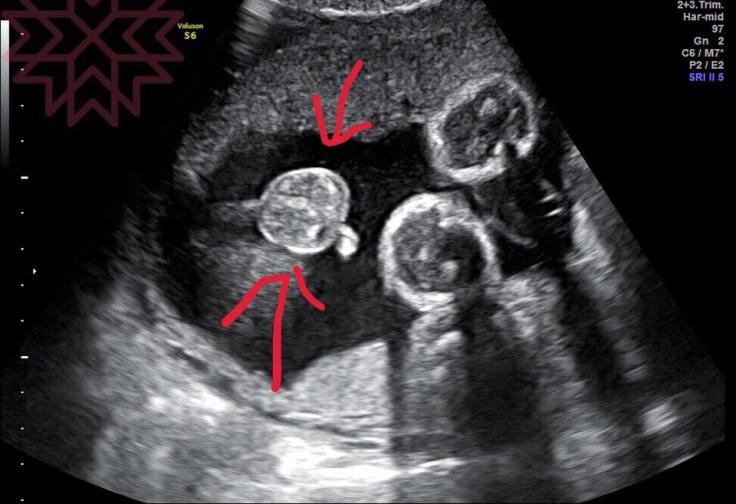

我們來聊聊男寶寶的睾丸

至於睪丸

就不一樣嘍

大約是要到懷孕七個月到八個月之間

才會掉到陰囊裡面

圖中箭頭那兩顆就是超音波下的小蛋蛋